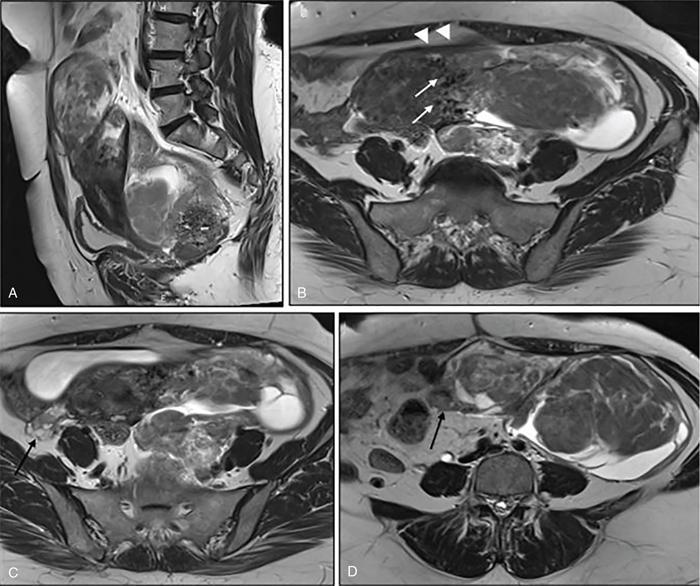

Suriyaprakash Nagarajan, Rupa Renganathan, Suhasini Balasubramaniam, Anupama Chandrasekharan, Kumarsampath Sumeena OVARIAN CYST VERSUS BLADDER Cystic lesions are common in female pelvis and mostly they originate from ovary. Ovarian cysts can arise from epithelial, stromal or germ cell components and can be benign or malignant cystic lesions. Pelvic Ultrasonography (USG) is the preferred imaging modality for evaluation of adnexal cystic lesions. Large simple ovarian cyst appears unilocular, anechoic with thin smooth walls. Such large simple cysts are confused with distended bladder. Distended bladder is a condition in which the urinary bladder is full and the patient is unable to void completely causing abdominal discomfort and pain. Distended bladder can be due to obstruction to passage of urine, neurological disorder or spastic sphincter. Differential diagnosis of cystic lesions in pelvis can be intraperitoneal, extraperitoneal and both intraperitoneal and extraperitoneal. Cystic lesions of intraperitoneal origin includes peritoneal inclusion cyst, paraovarian cyst, mucocele of appendix and hydrosalpinx. It is important to differentiate large simple ovarian cyst and distended bladder when patient presents with lower abdomen pain and the patient’s clinical history helps to make an accurate diagnosis (Table 11.4.1.1). UTERINE VERSUS EXTRAUTERINE MASS Ultrasound is usually the initial imaging modality for the pelvic mass. When USG findings are indeterminate to ascertain the organ of origin and to characterize, the next imaging modality is MRI due to its superior soft tissue resolution and multiplanar imaging capability (Figs. 11.4.2.1 and 11.4.2.2). Signs are demonstrated in Figs. 11.4.2.3 to 11.4.2.6. The sequences used in MRI pelvis are conventional T2WI in all three planes and T1WI in single plane. The problem-solving sequences are oblique coronal and oblique axial T2 along and perpendicular to the long axis of uterus in sagittal localizer. It can identify the organ of origin. Other sequences like T1 fat sat, diffusion-weighted imaging (DWI) and dynamic contrast T1WI with fat sat and subtracted images help to characterize the lesion further. BLADDER MASS VERSUS PROSTATE MASS Irregular mass lesions in the bladder neck are termed as ‘Bladder occupying lesions’. It is often difficult to determine whether the origin of these lesions is the bladder or the prostate gland. Transabdominal Ultrasound with colour Doppler studies and CT imaging do not usually delineate the origin of the lesions. The following features may aid in the differentiation (Table 11.4.3.1): History Painless haematuria Usually asymptomatic Investigations TAS, TRUS, MRI, Cystoscopy-guided biopsy PSA, DRE, TRUS, MRI, TRUS-guided biopsy At what point is the cross over between the two lesions T4 bladder cancer invading the prostate Aggressive prostate cancer protruding into the bladder Epicenter of the lesion Within the bladder Within the prostate gland Central necrosis in the mass Not commonly seen Seen in sarcomas IVU/CT urography Additional lesions in the urinary tract suggest that the bladder occupying mass in the bladder neck is of bladder-origin Prostate masses do not commonly cause masses in the urinary tract except for the very rare metastasis Virtual cystoscopy Additional lesions in the bladder wall and dome suggest that the bladder occupying mass in the bladder neck is of bladder-origin MRI T2 hypointensity Bladder masses are usually T2 hyperintense Seen in adenocarcinomas MRI T2 hyperintensity Bladder masses are usually T2 hyperintense Urothelial tumours infiltrating the prostate, neuroendocrine masses MRI T1 and T2 hyperintensity Bladder masses are usually T1 hypointense and T2 hyperintense Mucinous adenocarcinoma MRS Elevated choline values are seen in highly cellular masses Elevated choline:citrate ratio in prostate malignancies No significant finding in mucinous adenocarcinoma DWI Diffusion restriction is seen in malignant bladder masses No restriction in mucinous adenocarcinoma BPH versus bladder mass Exophytic BPH has signal intensities and appearance similar to and is contiguous with BPH within the gland OVARIAN MASS VERSUS PARAOVARIAN MASS Ultrasonography (USG) is the primary imaging modality in patients presenting with pelvic symptoms. Transvaginal, transabdominal or both should be performed in evaluation of such patients to differentiate ovarian and nonovarian origin of the lesions. Ovarian lesions can be a simple ovarian cyst, complex cyst with septations and solid components or a solid mass. Paraovarian lesions are remnants of the Wolffian duct in the mesosalpinx along fallopian tube or the ovaries and do not arise from the ovary. Paraovarian cysts are classified based on their site of origin into paratubal mesosalpingeal cysts, hydatid cysts of Morgagni, paraovarian cystadenoma and subserosal cysts. Differentiation of ovarian and paraovarian lesion poses significant diagnostic challenge. Both Computed tomography (CT) and Magnetic resonance imaging (MRI) are essential problem-solving tool in determining the site of origin of a pelvic mass. The first step in pelvic mass evaluation is to find out if it is ovarian or nonovarian in origin. Characterization of paraovarian or ovarian lesions is of utmost importance in order to optimize therapeutic procedures and it influences patients management (Figs. 11.4.4.1 and 11.4.4.2). Findings such as ovarian vascular pedicle sign, claw sign, bird beak sign and visualization of normal ovary helps to differentiate between ovarian and paraovarian lesions. Subsequently ovarian lesions should be categorized into benign, indeterminate and malignant masses (Table 11.4.4.1).

Ipsilateral ovary not seen separately from the lesion (Phantom sign) or the cyst is seen to arise from within the ovary (embedded organ sign).

Complete or incomplete septae often seen (Fig. 11.4.1.2A).

Ovarian cysts are anechoic lesions noted on one side of pelvis (Fig. 11.4.1.2B). Normal ovarian stroma can be seen around the cysts in case of small cysts.

Colour Doppler shows vascularity in the septum (Fig. 11.4.1.2C).

Solid components more commonly seen (Fig. 11.4.1.2D).